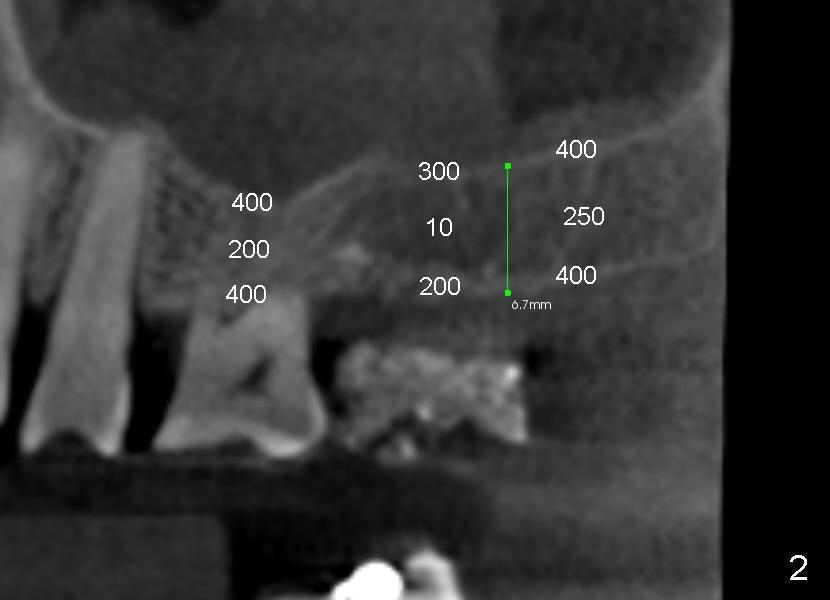

Davis is 53 years old.  This Wednesday an implant will be placed at the site of #2.  Since the case is complicated (involving multiple implant restoration), CT scan stent is fabricated using Calcium Sulphate (Fig.1 (sagittal section) S).  The stent helps treatment planning: placing 6x11 mm gingiva-level tapered implant in the most ideal restorative position (Fig.3,4 (coronal section)).  Since bone height is less than 7 mm (Fig.1), sinus lift is planned (Fig.3,4).

The density of the medullar area of the edentulous is so low (10) that the sinus floor (bone density 300) has to be used for primary stability of the implant.  Additionally, an osteotome may encounter resistance when it penetrates the crest (bone density 200; a cortical plate).  Once past the crest, tapping the osteotome through the cancellous bone should be easy until reaching the sinus floor (cortex).